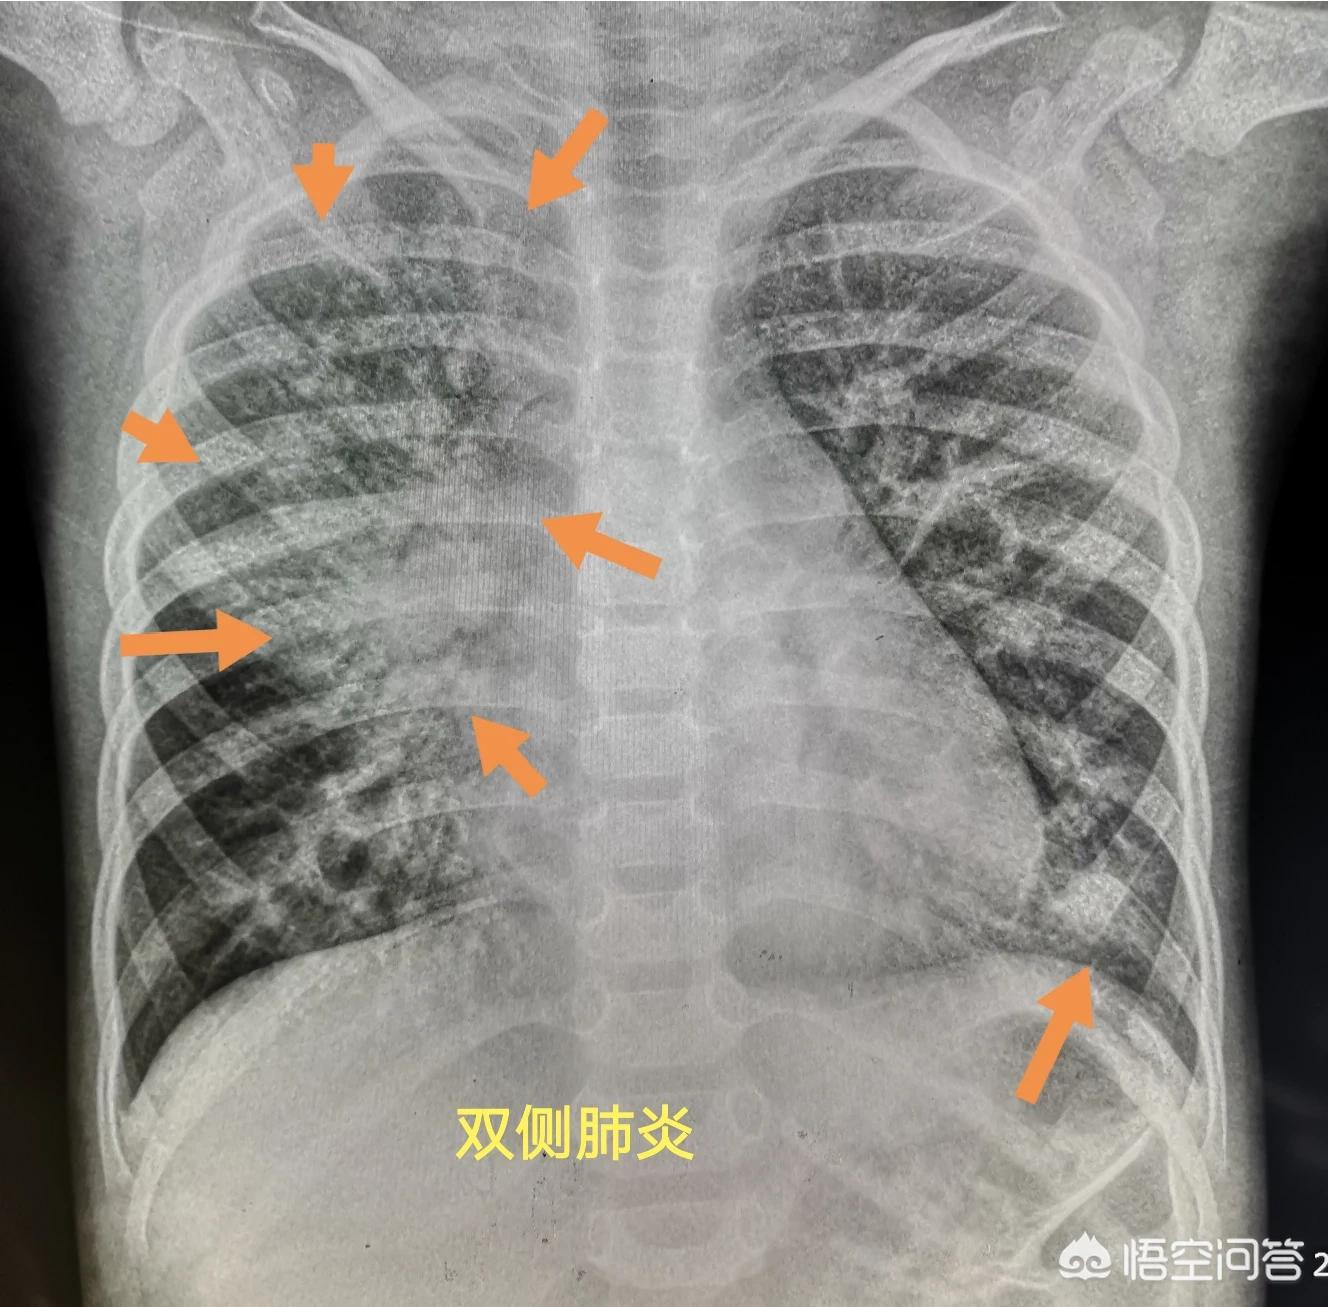

这位2岁小朋友咳嗽一周,发热三天,胸部拍片显示双侧肺炎,右侧面积很大,需要紧急住院治疗。